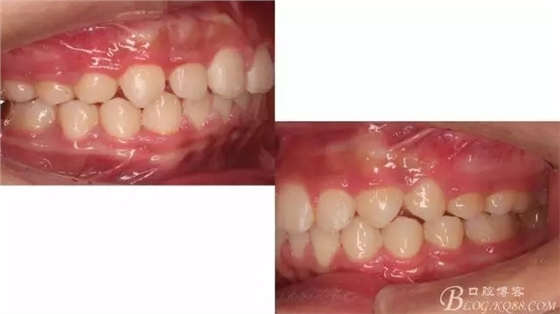

尖牙關系中性,磨牙關系中性,咬合鎖結良好!